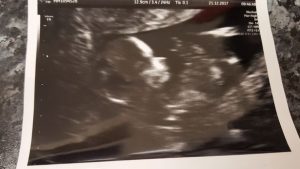

Kayleigh e seu parceiro, Steve Hopper, 32, fizeram seu primeiro ultrassom em novembro de 2017, que mostrou que seu bebê era perfeitamente saudável.

Mas a medida que a gravidez progredia e o casal foi para um ultrassom para descobrir o sexo, as anormalidades foram descobertas e ele estava crescendo sem qualquer líquido amniótico para protegê-lo.